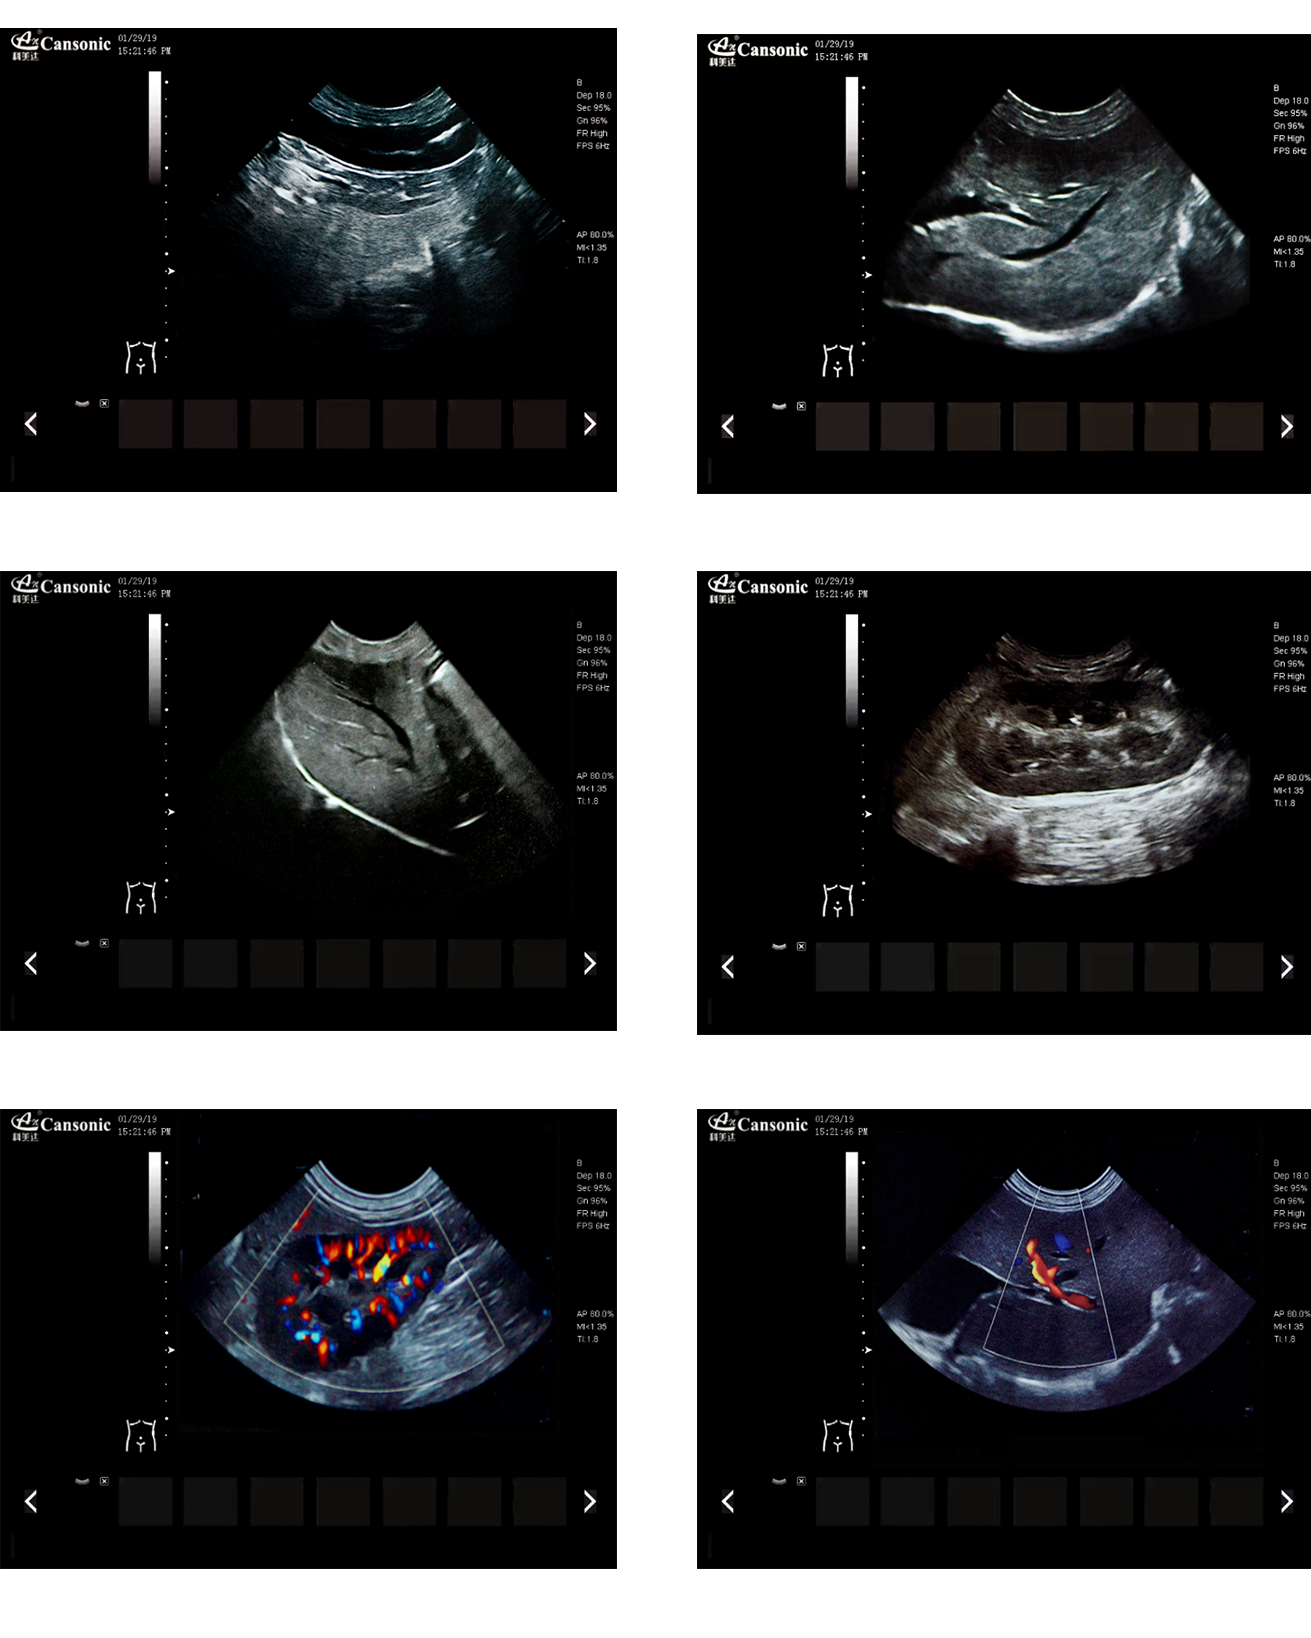

臨床圖示

產品特點:

1、薈萃前沿成像技術,實現(xiàn)高精與靈便的完美融合,提供完整的動物彩超診療方案

2、專業(yè)的獸用測量軟件,簡捷的工作流,適合犬、貓、馬、牛、羊等 各類大小動物

3、iClear斑點噪聲抑制抑制噪聲干擾,使動物組織結構更清晰

4、具有廣泛的動態(tài)范圍,顯示出色的組織均勻性,減少了偽影及噪聲

5、精細血流識別技術,增加了可疑病變更多的信息分析

6、先進的算法帶來清晰的穿刺針顯示,降低穿刺活檢操作難度

7、圖像優(yōu)異,同時性能穩(wěn)定,每天能進行大量的動物超聲檢查